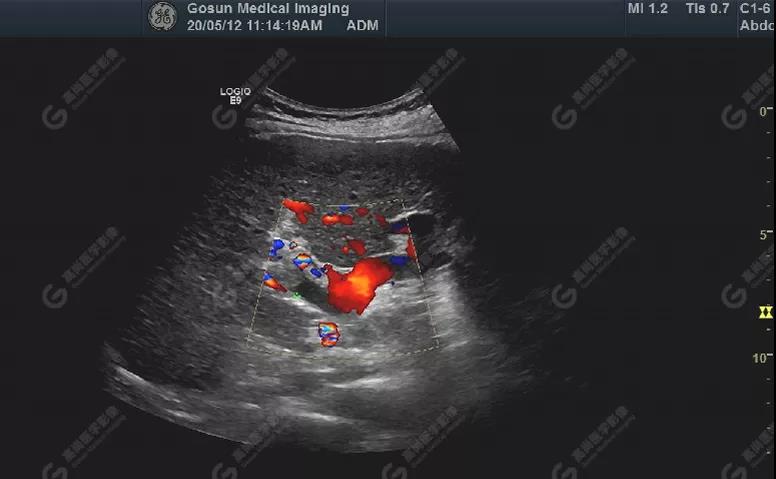

門靜脈右支內(nèi)低回聲處可見血流充盈缺損,其內(nèi)部無明顯血流

肝包膜不光滑,實(shí)質(zhì)回聲增粗,不均勻,以右葉顯著,肝內(nèi)可見散在高回聲結(jié)節(jié),最大約7mm×5mm,邊界清,形態(tài)規(guī)則,CDFI顯示高回聲結(jié)節(jié)未見明顯異常血流信號。門靜脈主干內(nèi)徑約14mm,門靜脈右支管腔內(nèi)見實(shí)性低回聲,大小約23mm×14mm,邊界不清,形態(tài)不規(guī)則,局部與肝組織分界不清,CDFI:門靜脈主干血流緩慢,左支血流充盈好,右支血流充盈缺損,低回聲內(nèi)未見明顯血流信號。超聲造影:經(jīng)左側(cè)肘靜脈團(tuán)注超聲造影劑sonovue2.0ml。肝組織開始增強(qiáng)時(shí)間8秒,病灶開始增強(qiáng)時(shí)間11秒,邊界清晰。脈期呈均勻高增強(qiáng),至門脈期和延遲期消退為低增強(qiáng)。延遲期肝S7段局部回聲減低,范圍約82mm×50mm,內(nèi)見一低增強(qiáng)區(qū),范圍約13mm×16mm。